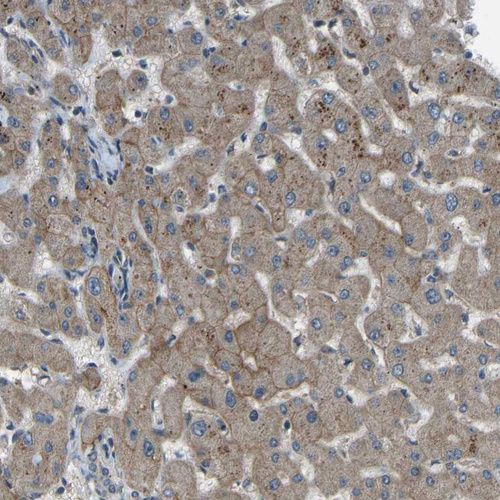

Immunohistochemical staining of human pancreas shows strong membranous positivity in exocrine glandular cells.